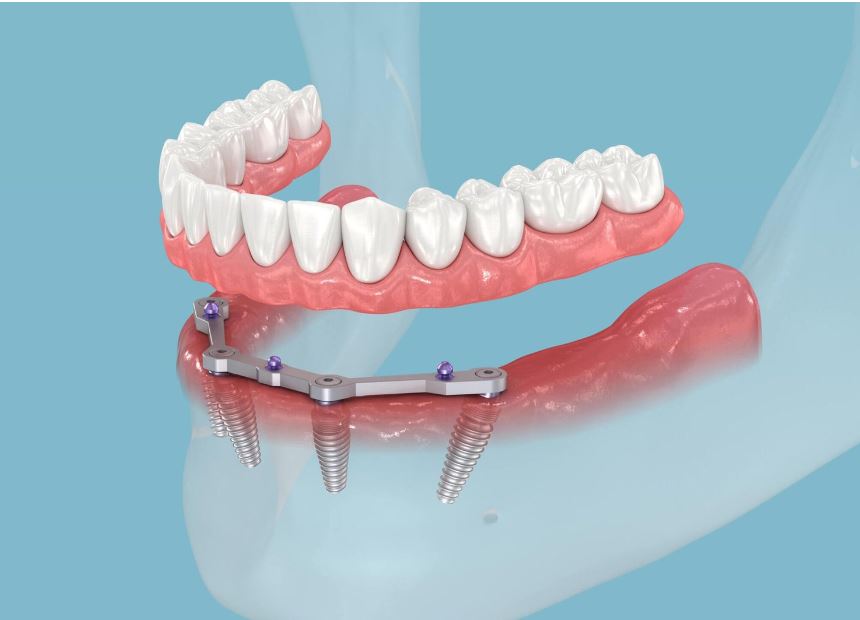

Phương pháp Implant toàn hàm All on 4

Phương pháp Implant toàn hàm All on 4

Implant All on 4 là một giải pháp cấy ghép răng implant tiên tiến, được phát triển nhằm cung cấp một phương án hiệu quả để khắc phục tình trạng mất răng toàn hàm. Khác với các phương pháp truyền thống, Implant All on 4 chỉ yêu cầu 4 implant trên mỗi hàm răng, cùng với việc lắp đặt một cầu răng tháo lắp hoàn chỉnh.

- Không phải cấy ghép nhiều trụ Implant, giảm sưng đau: Đối với kỹ thuật cấy Implant All On 4, chỉ cần 4 trụ Implant đã có thể giúp khôi phục cả hàm răng chắc chắn. Đây là giải pháp hàng đầu cho bệnh nhân mất răng toàn hàm, tiêu xương nhiều – vừa tiết kiệm tối đa chi phí, vừa giảm bớt sưng đau khi cấy ghép.